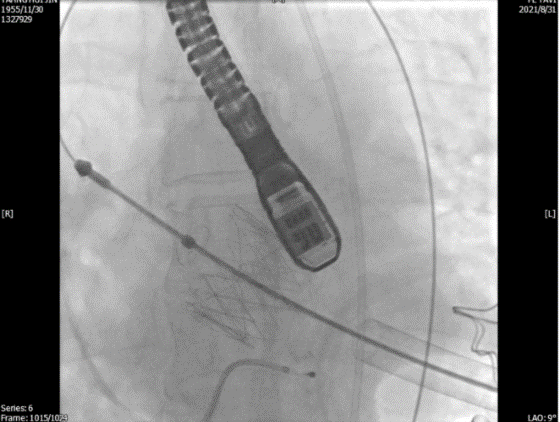

单弯管交换硬导丝后,用16F扩张鞘预扩心尖穿刺处,将 J-valve瓣膜(27号)装入输送器,将输送器推送至主动脉根部(通过零造影剂DSA确认),释放定位件,患者无需起搏,适当调整定位件角度使其进入三个主动脉窦部(图3)。

图3. TEE和放射线显示定位件入窦,人工瓣入座